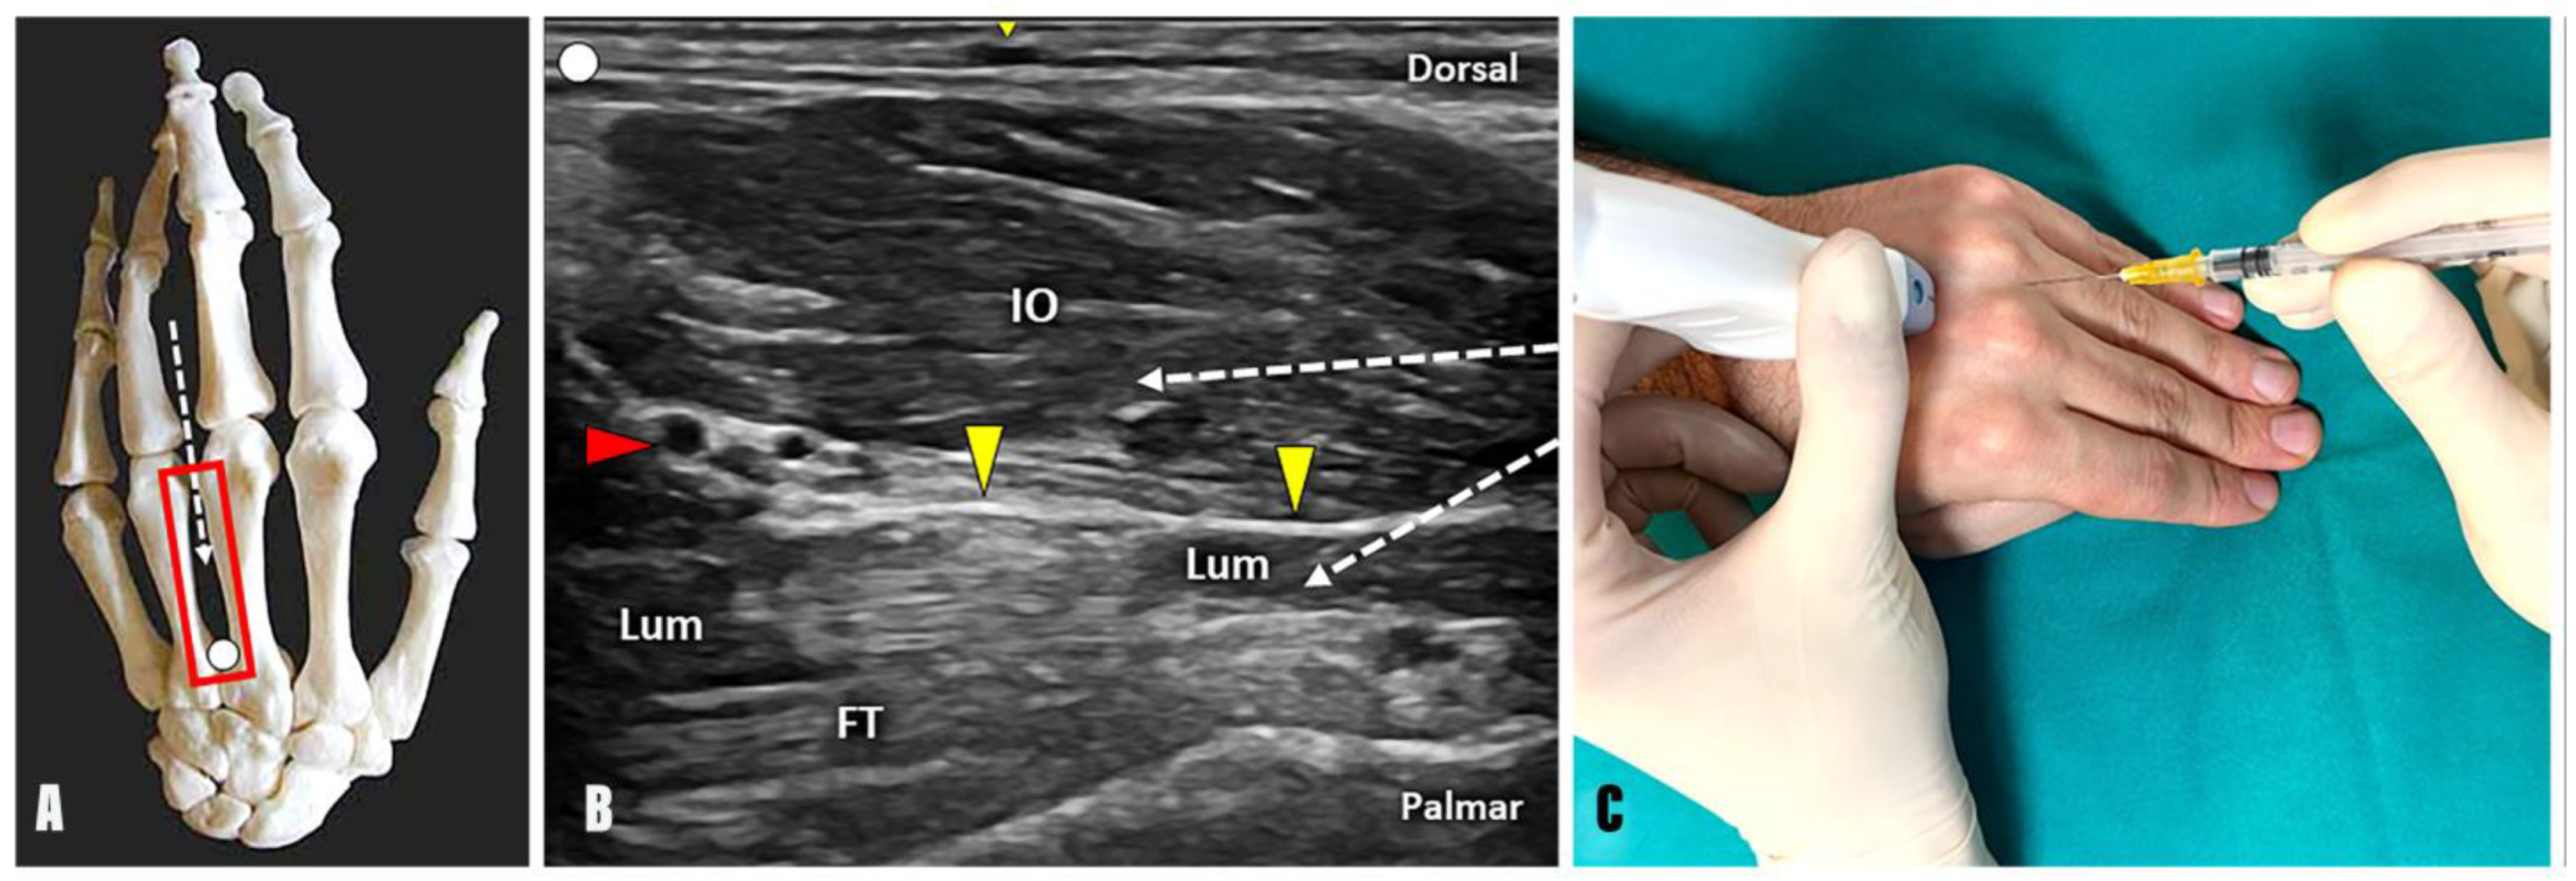

- Technique: Positioning the probe in a longitudinal plane over the dorsal aspect of the intermetacarpal space, the needle can be advanced using an in-plane technique and a distal-to-proximal approach within the most superficial muscular compartment, which represents the dorsal and palmar interosseous muscles (Figure 3).

- Tips and tricks: Interestingly, the anatomical arrangement of the interosseous muscles within the second intermetacarpal space makes the distinction between dorsal and palmar one quite reliable, as they lie parallel to each other in the longitudinal axis. Likewise, their arrangement does not follow the same spatial pattern in the third and fourth intermetacarpal spaces, arranging themselves next to each other or twisting together. Moreover, individual anatomical variability makes the distinction of muscle boundaries even more complicated in such a small anatomical district as the intermetacarpal interval [26]. In the authors’ experience, the BTX injection of the interosseous muscle “complex” ensures accurate management of hand spasticity without the need to distinguish between the dorsal and palmar components.

- Technique: Positioning the probe in a longitudinal plane over the dorsal aspect of the intermetacarpal space, the needle can be advanced using an in-plane technique and distal-to-proximal approach within the lumbrical muscles (Figure 3). Interestingly, a thin hyperechoic fibrofatty band is located between the interosseous and lumbrical muscles and can be used as a sonographic landmark to optimize the accuracy of the procedure. Likewise, a dynamic scanning with passive/active mobilization of the fingers can be performed to observe a differential gliding of the interosseous and lumbrical muscles within the intermetacarpal space (Supplementary Video S2).

- Tips and tricks: Using the B-mode, a small vascular bundle can be identified within the hyperechoic fat pad between the interosseous and lumbrical muscles (Figure 3). Using color Doppler, a small vascular bundle is observed between the interosseous and lumbrical muscles within the third intermetacarpal space. Therefore, a color Doppler assessment of the intermetacarpal space should always be performed before the injection to avoid unintentional bleeding and iatrogenic injuries to the hand vasculature (Supplementary Video S3).